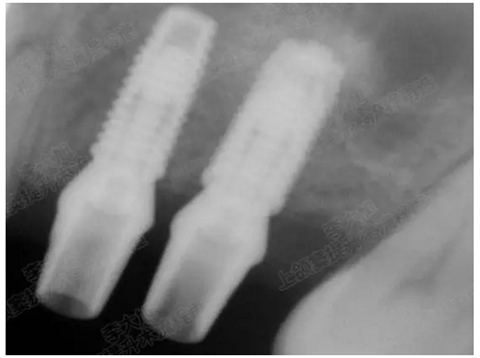

05.png

提升8mm

06.png

07.png

修復(fù)時(shí)根尖片

08.png

09.png